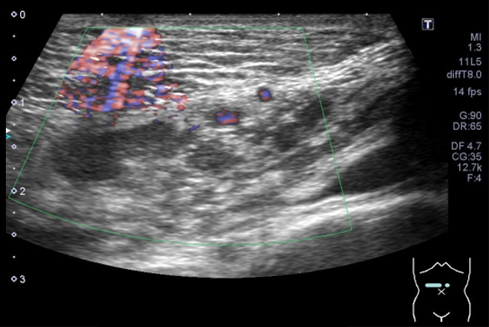

疼痛部のUS T